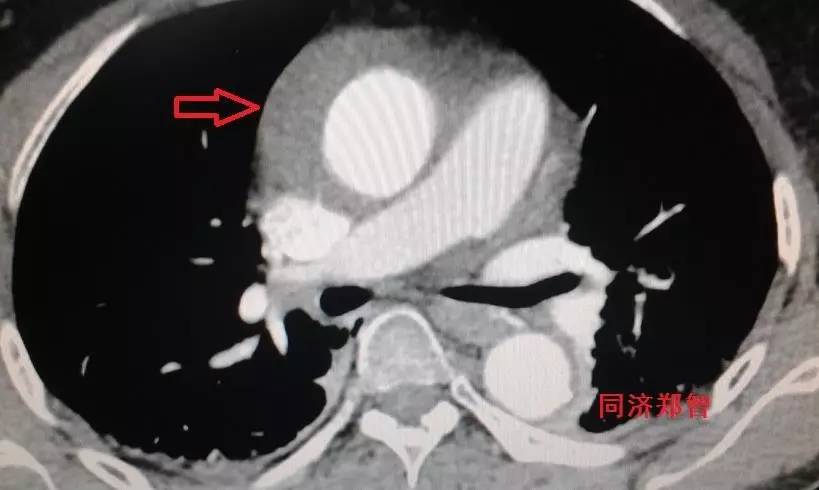

胸降主动脉穿透性溃疡合并壁间血肿(图6),心底层面红箭头所示。

图6

CTA三维重建,红箭头显示胸降主动脉穿透性溃疡合并壁间血肿(图7)。

图7